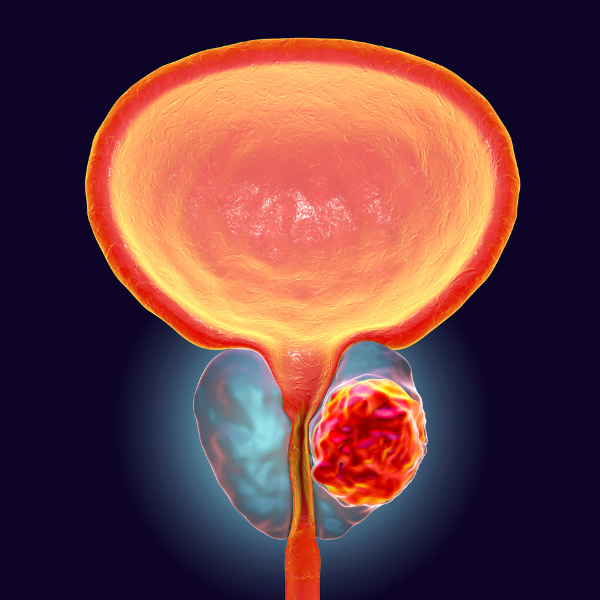

Examen clinique et échographique

Dr ZEKRI, expert en soins urologiques à Bachdjerah, commence par un examen clinique complet accompagné d’une échographie ciblée. Cette évaluation initiale permet de localiser d’éventuelles anomalies au niveau de la vessie, des reins ou de la prostate, pour proposer une prise en charge adaptée dès la première consultation.